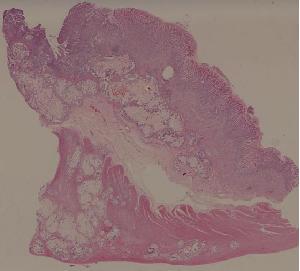

61.胃腺癌(胃粘液腺癌)

友情链接: